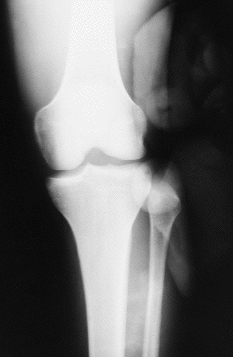

La exploración radiológica simple era sugestiva de un desplazamiento anterolateral de la cabeza del peroné. No se realizó TC (Figs. 1 y 2).

Fig. 1.--Radiografía anteroposterior de rodilla. Se observa desplazamiento anterolateral de la extremidad proximal del peroné. Anteroposterior X-ray of the knee. It shows anterolateral displacement of the proximal end of the fibula.